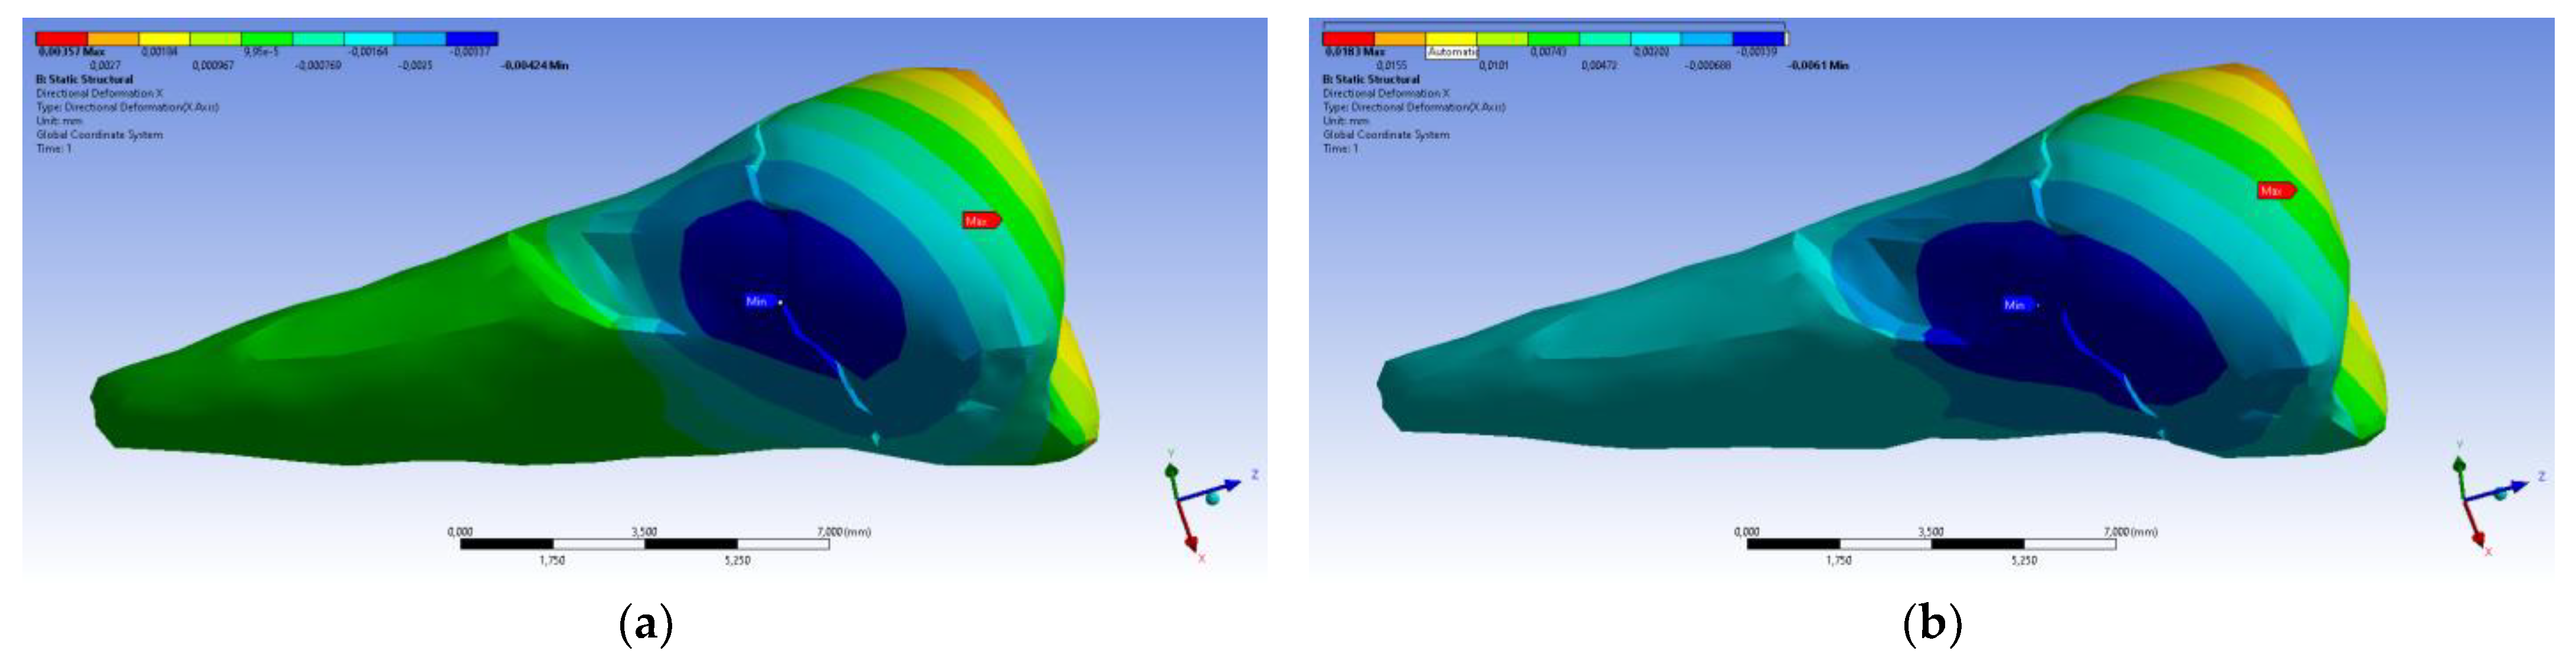

3. Finite Element Analysis (FEA) of Mandibular Right Premolars

| Total Deformation | Deformation in X Direction | Deformation in Y Direction | Deformation in Z Direction | Equivalent Stress | Normal Stress X | Normal Stress Y | Normal Stress Z | Maximum Main Stress | Minimum Main Stress | Tangential Stress XY | Tangential Stress YZ | Tangential Stress XZ | |

|---|---|---|---|---|---|---|---|---|---|---|---|---|---|

| Minimum | 0 mm | −4.24 × 10−3 mm | −2.52 × 10−2 mm | −1.56 × 10−2 mm | 1.01 × 10−6 MPa | −35.6 MPa | −57.1 MPa | −104 MPa | −15.2 MPa | −152 MPa | −43.7 MPa | −39.6 MPa | −56.3 MPa |

| Maximum | 2.77 × 10−2 mm | 3.57 × 10−3 mm | 6.98 × 10−4 mm | 4.78 × 10−3 mm | 248 MPa | 61.5 MPa | 177 MPa | 72.2 MPa | 195 MPa | 21.4 MPa | 44.2 MPa | 117 MPa | 22.2 MPa |

| Minim. in | Cementum | Cementum | Enamel | Enamel | Cementum | Cementum | Enamel | Enamel | Enamel | Cementum | Enamel | Enamel | Cementum |

| Maxim. in | Enamel | Enamel | Cementum | Enamel | Cementum | Enamel | Enamel | Enamel | Enamel | Enamel | Cementum | Cementum | Cementum |

| Total Deformation | Deformation in X Direction | Deformation in Y Direction | Deformation in Z Direction | Equivalent Stress | Normal Stress X | Normal Stress Y | Normal Stress Z | Maximum Main Stress | Minimum Main Stress | Tangential Stress XY | Tangential Stress YZ | Tangential Stress XZ | |

|---|---|---|---|---|---|---|---|---|---|---|---|---|---|

| Minimum | 0 mm | −6.1 × 10−3 mm | −9.02 × 10−2 mm | −3.99 × 10−2 mm | 1.02 × 10−6 MPa | −112 MPa | −199 MPa | −278 MPa | −65.5 MPa | −470 MPa | −148 MPa | −176 MPa | −178 MPa |

| Maximum | 9.28 × 10−2 mm | 1.83 × 10−2 mm | 1.38 × 10−3 mm | 3.12 × 10−2 mm | 780 MPa | 61.5 MPa | 649 MPa | 304 MPa | 704 MPa | 73.8 MPa | 134 MPa | 370 MPa | 78.6 MPa |

| Minim. in | Cementum | Cementum | Enamel | Enamel | Cementum | Cementum | Enamel | Enamel | Enamel | Cementum | Enamel | Enamel | Cementum |

| Maxim. in | Enamel | Enamel | Cementum | Enamel | Cementum | Enamel | Enamel | Enamel | Enamel | Enamel | Cementum | Cementum | Cementum |